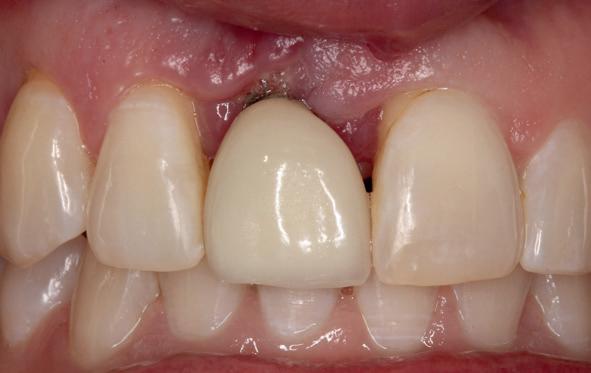

Implantologische behandelingen in het esthetische front vragen meer dan technische vaardigheid alleen. Ze vragen om overzicht, timing, vertrouwen en een team dat als vanzelf samenwerkt onder druk. Juist bij complexe casussen, waarin angst, infectie en hoge esthetische verwachtingen samenkomen, wordt zichtbaar hoe bepalend de rol van de tandartsassistent is.

Deze casus beschrijft een uitgebreide immediate implantaatbehandeling bij een patiënt die door meerdere collega’s werd geweigerd. Niet omdat de mogelijkheden ontbraken, maar omdat de complexiteit vroeg om een perfect afgestemde samenwerking. Het verhaal laat zien hoe de assistent in zo’n traject veel meer is dan een uitvoerende kracht of “mal”, maar een dynamische surgical guide die het proces mede stuurt, bewaakt en mogelijk maakt.De patiënt: wanneer alles samenkomt

Ze kwam binnen op een dinsdagochtend, iets voor achten. Een vrouw van begin zeventig, met een zachte stem en ogen die meer vertelden dan haar woorden. Ze vertelde dat ze een eigen B&B had en dat ze zich nauwelijks kon voorstellen gasten te ontvangen zonder tanden. Op dit moment kon ze echter nauwelijks lachen. “Het doet pijn… en het ruikt soms ook niet goed,” zei ze bijna verontschuldigend. Haar oude bovenbrug, die ze al meer dan twintig jaar droeg, was langzaam maar zeker ingestort. Er was sprake van cariës onder meerdere pijlers, pusafvloed,

chronische ontsteking en een brug die mobiel was en elke beet pijnlijk maakte. Ze had inmiddels meerdere tandartsen bezocht. Drie hadden haar geweigerd. Te complex. Te veel wensen. Te onvoorspelbaar.

De kern van haar vraag was eenvoudig en tegelijkertijd uitdagend: Is het mogelijk om mijn huidige brug te dupliceren en een nieuwe brug te vervaardigen met minder complicaties?

De basis van een complexe beslissing

Mijn behandelplan begint altijd met een uitgebreid klinisch onderzoek. Dat omvat een medische anamnese, intra- en extra-orale camerafoto’s en uitgebreid verwachtingsmanagement. In deze fase is mijn assistent vooral bezig met het zorgvuldig vastleggen van alle gegevens. Juist dat nauwkeurig documenteren zorgt voor rust in de behandelkamer. Minstens zo belangrijk is het luisteren naar de patiënt. Niet alleen naar de klachten, maar naar het

1. Extra-orale foto (lachlijn).

2. Beoordeling van zacht weefsel en botcontour.

3. Reflectiefoto – beoordeling van occlusievlakken en tandboog.

4. Pre-chirurgische OPG.

levensverhaal en de mens achter de brug. Begrijpen wat deze behandeling voor iemand betekent, is cruciaal voor het uiteindelijke succes.

Na het klinische onderzoek volgde het röntgenologisch traject. De CBCT liet precies zien wat we al vreesden: een front waarin het bot onregelmatig was, duidelijke radiolucenties rond de pijlers en een infectiegebied dat zich onder vrijwel de gehele brug had verspreid. Tegelijkertijd was er ook potentie. Net voldoende botstructuur om immediate implantaatplaatsing te overwegen, mits alles perfect gepland zou worden.